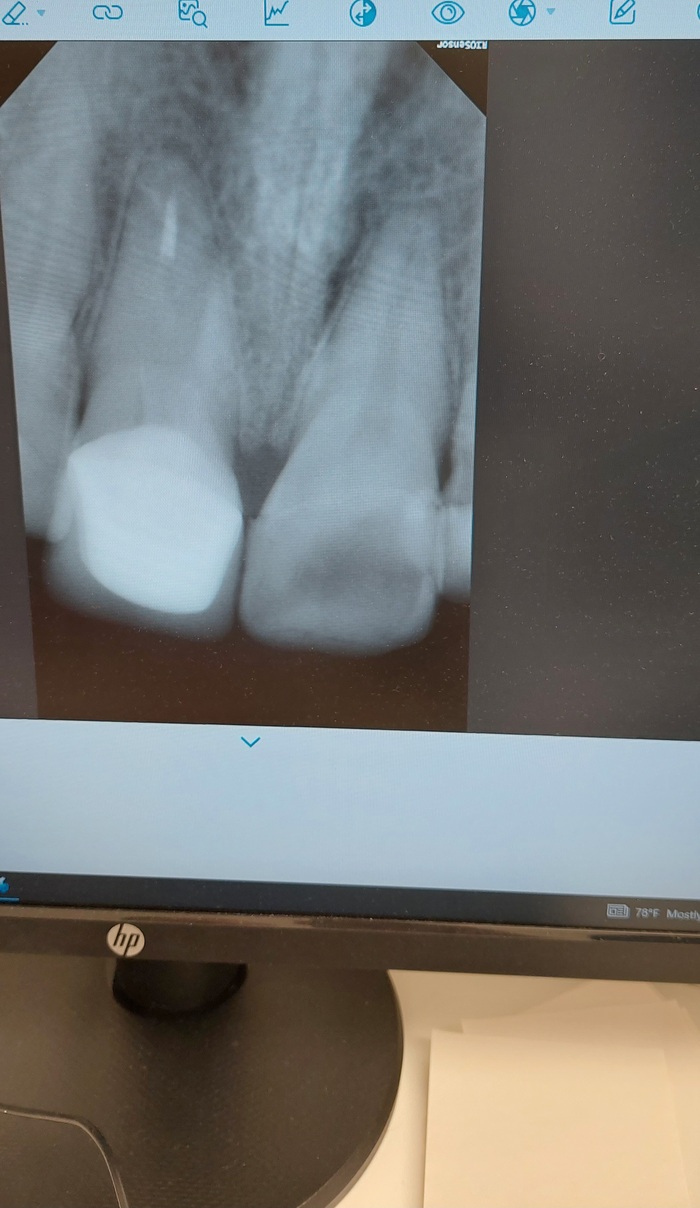

что имеем(грустное): по 3 раскрошенных зуба в местах боли. Боль гуляет, то низ болит остро, то верх сильнее, начиналось сверху.

2) рентген сделаю, что ещё нужно? КТ или что? С чем в итоге на прием лучше бежать сразу, чтобы уже быстрее развивались события?